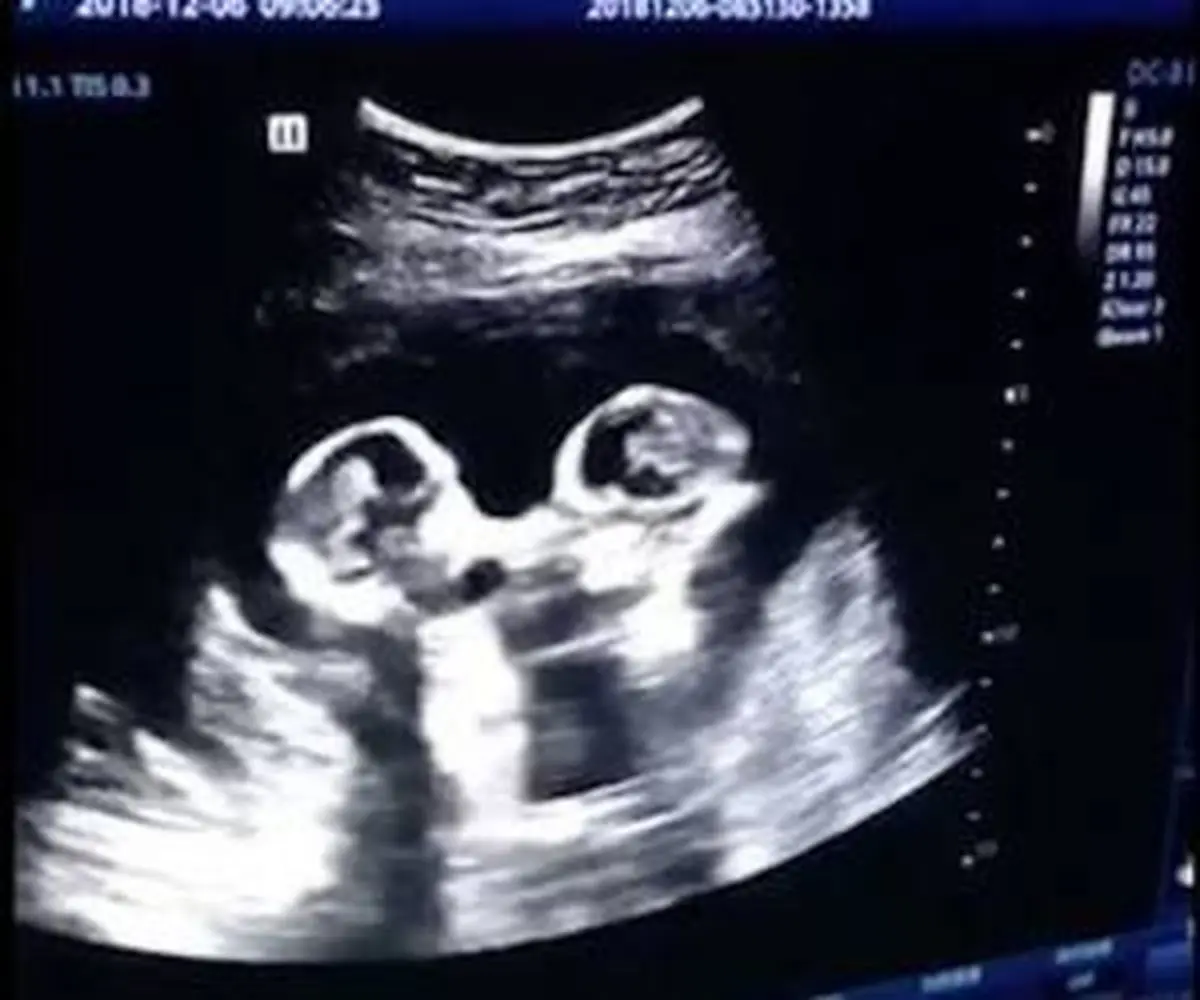

مادر جوان چینی که دو جنین را در یک رحم باردار بود، اخیرا ویدیویی را از سونوگرافی خود منتشر نمود که توانست با بازتاب فراوانی روبرو شود.

مادر چینی زمانیکه برای بررسی جنین های دوقلو خود به بیمارستان ینچوآن چین مراجعه کرد، تحت سونوگرافی قرار گرفت که در این سونوگرافی دو جنین بازیگوش که در رحم مادر قرار داشتند، بطرز عجیبی با یکدیگر در رحم مادر در حال کتک کاری و مبارزه بودند. این ویدیو در دسامبر گذشته ضبط شده است و اخیرا توسط پدر و مادر این دو جنین منتشر شدند.